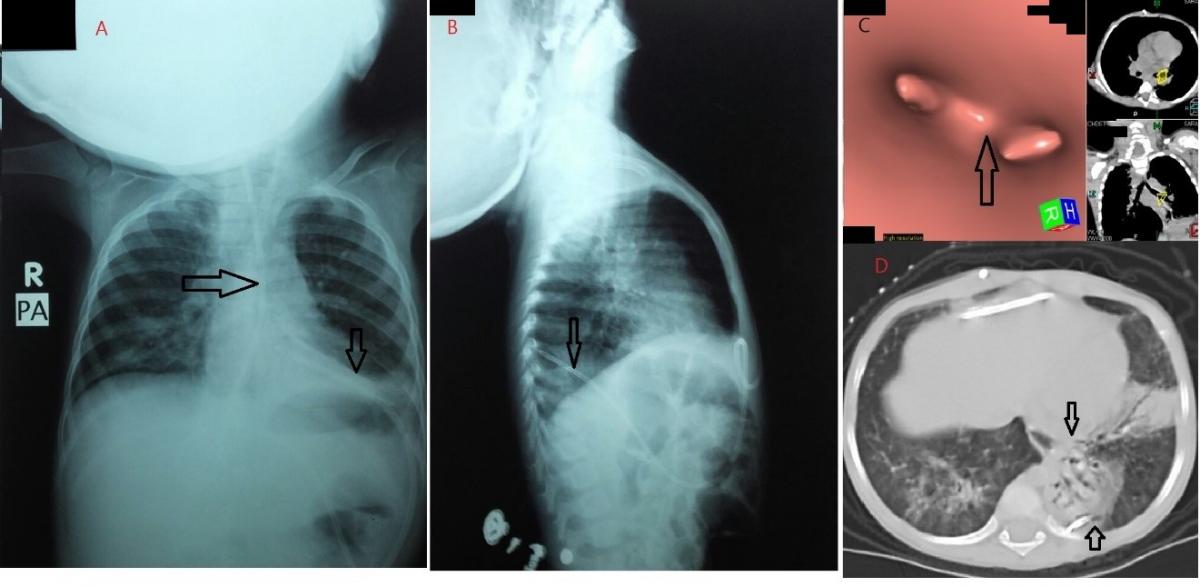

Figure 1. VP shunt in the left lower lobe of lung piercing left copula of diaphragm. A and B) PA and lateral chest x-ray. C and D) MSCT chest, pulmonary and tracheobronchial reconstruction windows.

A 2-year-old girl with congenital hydrocephalus had a VP shunt that had been inserted from 1 year. The patient presented with recurrent chest infection and productive cough for 10 months. Also, she suffered from intermittent attacks of vomiting and diarrhea over 2 months duration. On evaluation, the patient was expectorating a clear watery sputum. A chest x-ray revealed radio-opaque catheter emerging from the abdomen into the left lower hemithorax. Chest computed tomography revealed abnormal migration of the VP shunt in the left lower lobe of lung and piercing left copula of diaphragm, with bronchiectatic changes and pneumonic consolidation of left lower lung lobe.